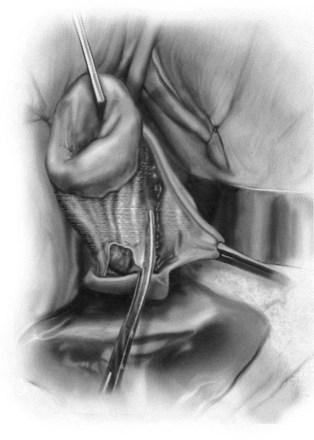

Groutz and colleagues (2001) prospectively enrolled 21 women with grade 3 or 4 anterior vaginal wall prolapse to cystocele repair using solvent dehydrated cadaveric fascia lata (Fig. 72–19). The graft was anchored transversally between the bilateral arcus tendineus and the cardinal and uterosacral ligaments. Also, 19 of the 21 women underwent concomitant pubovaginal sling for either symptomatic or occult SUI. After a mean follow-up 20 months, none of the patients developed a recurrent cystocele. In addition, no patient developed new-onset dyspareunia, pelvic pain, or postoperative vaginal stenosis.

Figure 72–19 Anterior compartment repair with cadaveric fascia graft. Cadaveric fascia patch was tailored appropriately. Typically a 5- × 7-cm patch is more than adequate.

(From Groutz A, Chaikin DC, Theusen E, et al. Use of cadaveric solvent-dehydrated fascia lata for cystocele repair—preliminary results. Urology 2001:58:179–83.)